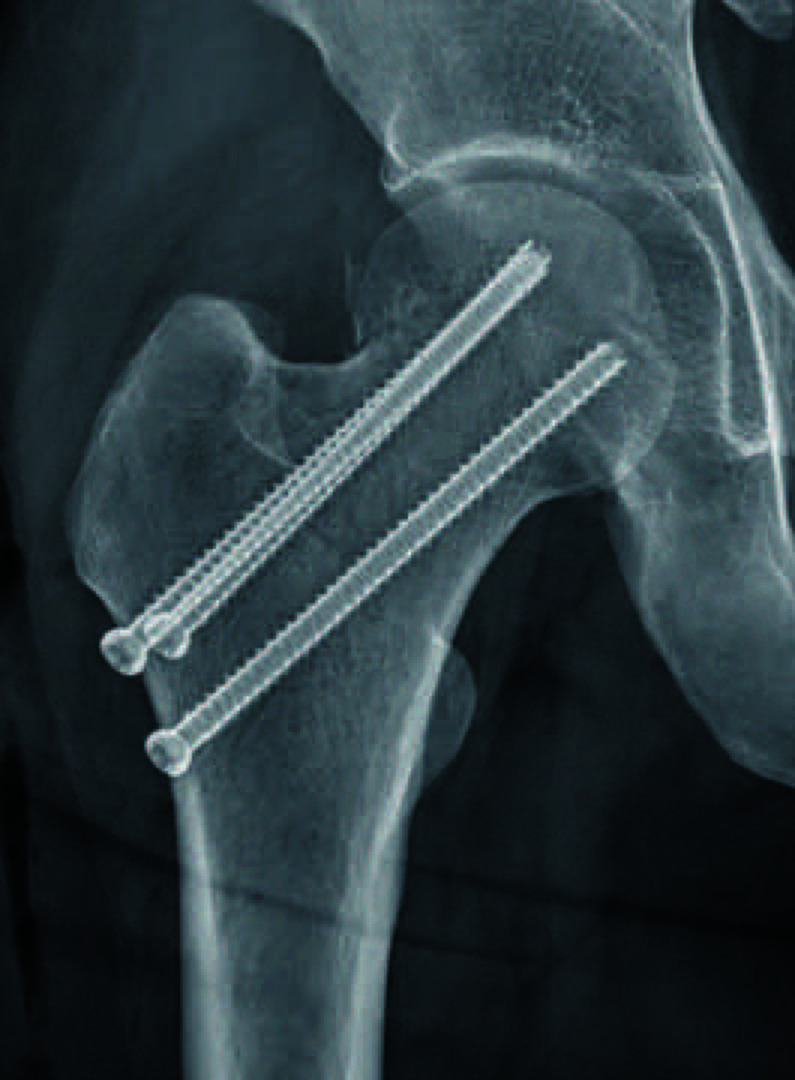

Materials and methods: Patients who underwent internal fixation using multiple cannulateld screws for management of nondisplaced femoral neck fractures were divided into two groups: high valgus group (postoperative valgus angle ≥15°) and low valgus group (postoperative valgus angle <15°). Evaluation of demographic data and changes in the joint space width from the immediate postoperative period to the latest follow-up was performed.

Results: A significant decrease in joint space width in both hip joints was observed in the high valgus group when compared with the low valgus group, including cases with an initial valgus angle less than 15° and those corrected to less than 15° of valgus by reduction. No complications requiring surgical treatment were observed in either group; however, two cases of avascular necrosis, one in each group, which developed in the low valgus group after reduction of the fracture, were followed for observation.

Conclusion: Performing in situ fixation in cases involving a valgus deformity ≥15° in non-displaced femoral neck fractures may cause accelerated narrowing of the hip joint space.